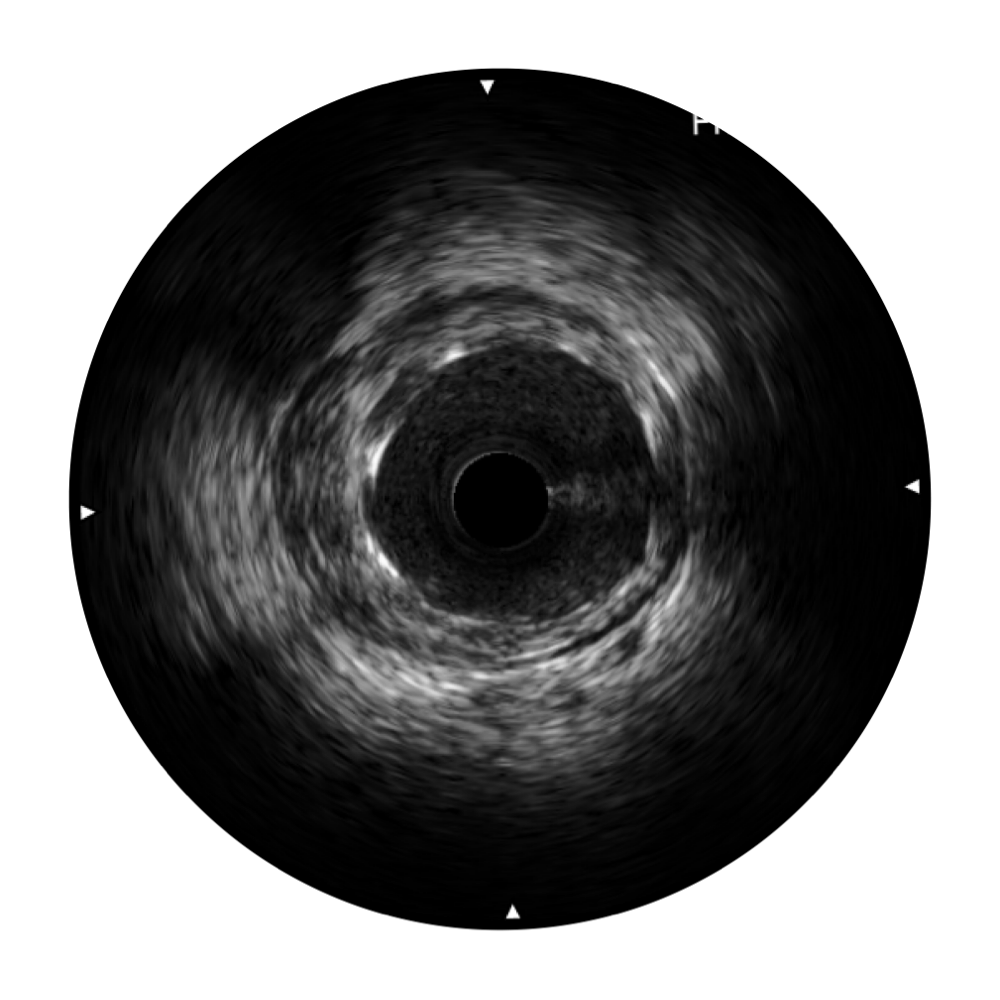

• 16877太阳集团宽频IVUS图像

• 传统IVUS图像

对比传统IVUS导管成像,16877太阳集团宽频IVUS图像的近场支架梁显影更细腻,远场中膜外血管仍清晰可辨,兼顾远中近,兼顾分辨力与穿透深度